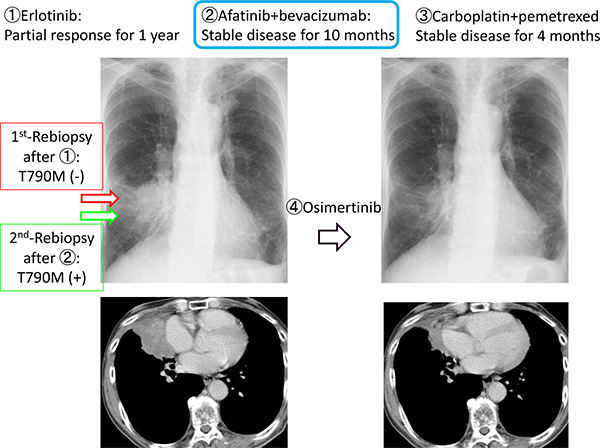

We herein describe a representative case of T790M-positive conversion. The patient was 73 years-old male with EGFR-mutant (L858R) NSCLC. He received erlotinib as the first-line therapy for 1 year. After progression, rebiopsy was performed using bronchoscopy. T790M was negative, then ABC-therapy and carboplatin plus pemetrexed were administered as second- and third-line chemotherapies. After further progression, rebiopsy was carried out again to the same lesion and procedure. T790M was converted to positive, and osimertinib was initiated. Partial response was confirmed, and TTF was 12.2 months (Figure 3).

Figure 3: Presentation of case #6.